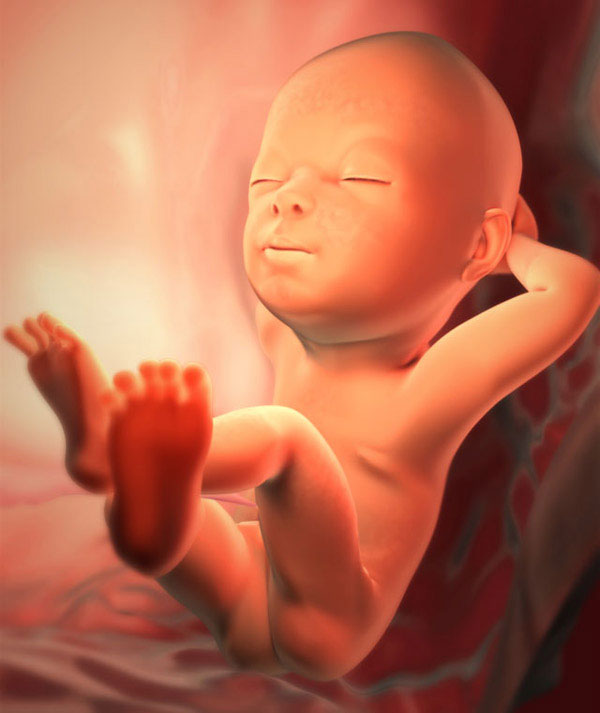

fetal size at 29 weeks gestation

Now the baby just grows and consolidates earlier achievements. The most active development of subcutaneous fat continues, and not only the usual one that any person has. The fetus also forms a special brown fat. When the baby is born, this substance will perfectly protect it from the cold. This is important, since heat regulation in newborns is not immediately established.

How is the fetus located now? Many children have already settled correctly, that is, head down. But the position of the baby's body may not yet once change before the birth. Now there is no reason to worry. When two children immediately grow up under the mother’s heart, they are more cramped, less room for coups. But the twins at this period do not always occupy the right position.

fetus at 29 weeks of gestation